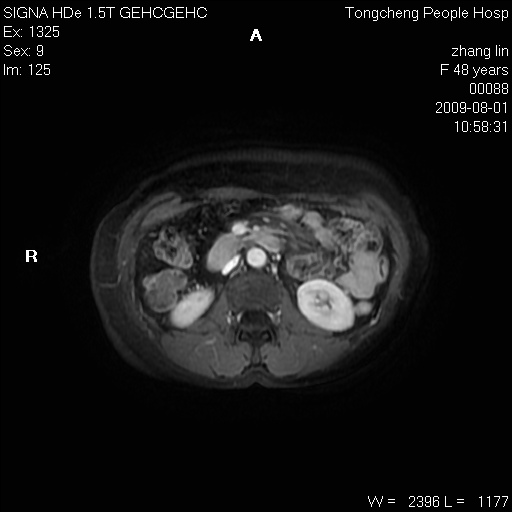

女,48岁。健康体检,彩超发现右肾占位性病变。平素健康。

临床诊断:右肾占位性病变,性质待定(囊肿?肿瘤?)。

上中腹部mr平扫+增强扫描,图像如下:

右肾上极见一类圆形病灶,t1wi呈等信号t2wi呈等高混杂信号,三期增强无强化,边界清---考虑囊肿出血。

同反相位均表现为等信号,病变无强化,考虑含蛋白的囊肿可能,弥散加权相或许有些帮助,